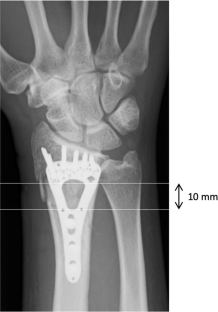

A total of 10 fracture sites identified from four patients with a distal radius fracture who underwent internal fixation with a volar locking plate (mean age 68.8 years, all women) were investigated. HR-pQCT was performed within a week (baseline) 4, 12, and 24 weeks after fracture. Rectangular region of interest (ROI) was established in the fracture site, inner callus, and external callus area, and the changes in bone mineral density (BMD) in each region were analyzed.

Fig. 1